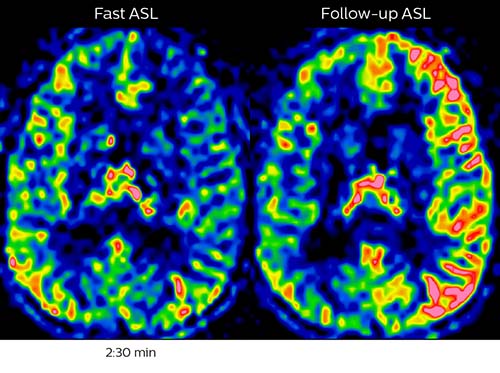

Comprehensive stroke MRI within acceptable time

Dr. Savatovsky appreciates the improvements and flexibility that Elition with Compressed SENSE and MultiBand SENSE provides, particularly for stroke patients. “For stroke, it allows us to cut about 5 minutes off of our stroke protocol, or to keep the same acquisition time and get more insights.” The ability to perform more sequences can help in making a swift and confident diagnosis. “For example, our stroke cases usually include the regular sequences that every center does (b1000 diffusion, FLAIR, time-of-flight angiography), but we also image supra aortic vessels, and we can replace a gradient echo sequence with a fast 50-second susceptibility-weighted sequence, and all of this doesn’t add much time. because all the regular sequences are accelerated on Elition.” “The time savings with Compressed SENSE and MultiBand SENSE make it easier to add sequences to give us additional insights. Depending on the context and the first results, we might add a DSC perfusion to assess the ischemic penumbra, an ASL perfusion to help find an alternative cause in case of normal diffusion, or add a high-resolution T1 sequence for a stroke patient, to quickly assess wall imaging in emergency cases. The additional sequences can help improve patient management, because we can already consider some alternative diagnoses if the morphological MRI is normal.”

In this patient with acute right motor deficit and aphasia, the b2000 diffusion weighted image is normal. The SWIp image demonstrates more prominent veins in the right hemisphere, which could reflect increased deoxyhemoglobin contents. Fast ASL shows low CBF regions in the left frontal lobe. A follow-up ASL after one hour demonstrates high CBF values in the same area. The final diagnosis was migraine with aura.